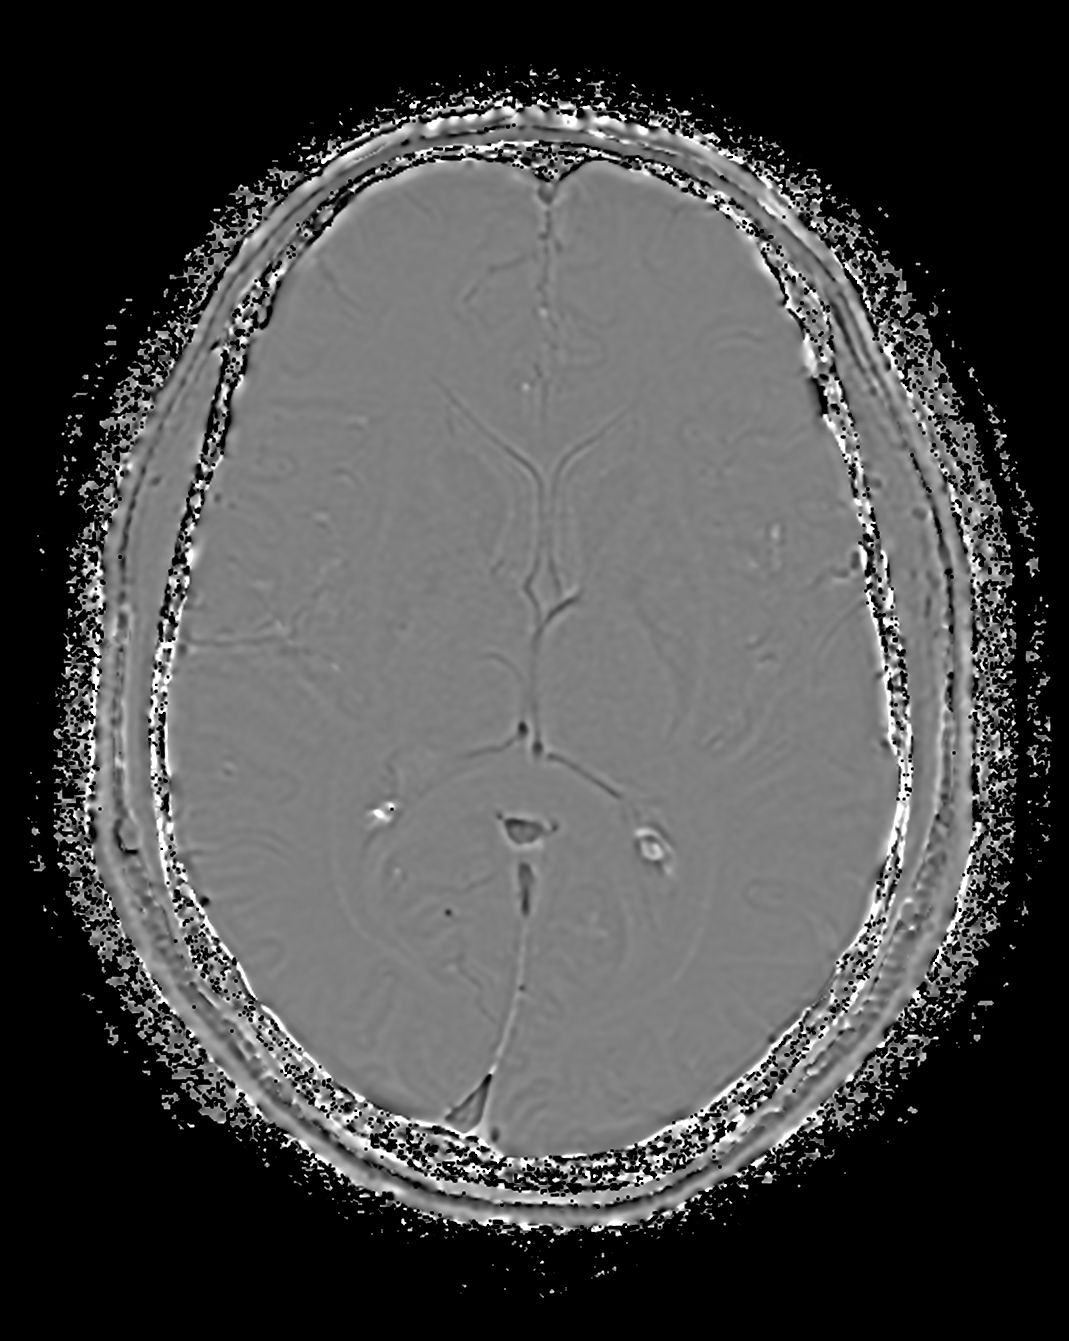

Alzheimer’s Disease Anti-Amyloid Immunotherapies (ARIA) 1.5T

Amyloid clearing medication, such as Aduhelm (Aducanumab) and Leqembi (Lecanemab) have been cleared by the FDA in 2022/2023, to slow down cognitive decline in early-stage Alzheimer’s disease. ASNR-recommendations for AD therapeutic imaging were published in 2022 for eligibility assessment as well as for monitoring for amyloid-related imaging abnormalities. This ExamCard includes ASNR-recommended consensus protocols for imaging of Alzheimer’s Disease Anti-Amyloid Immunotherapies (ARIA). (Cogswell et al., AJNR 2022,43(9)E19-E35;DOI: https://doi.org/10.3174/ajnr.A7586))